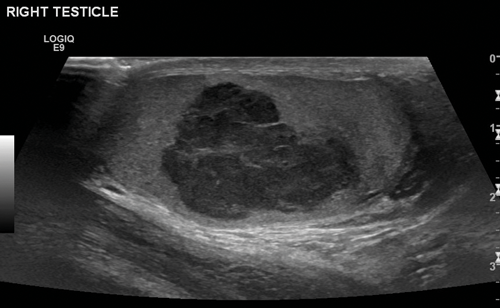

Figure 1. US of seminoma seen as a multi-septated area of low attenuation with a lobulated outline.

Seminomas can have a uniform appearance and are generally of low echogenicity but larger tumours may be heterogenous and lobulated (Figure 1). Typically, teratomas are described with areas of calcification and are heterogenous, also containing fluid. They can have areas of central necrosis and haemorrhage (Figure 2). Both tumours are classically hypervascular, but depending on areas of fluid or necrosis may be hypovascular. Lymphoma tends to be infiltrative involving the whole testis and causing diffuse testicular enlargement rather than a more focal tumour.